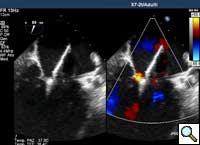

Figure 7

In absence of controlled clinical trial data which are forthcoming from the EVEREST II randomized study, the indications for the MitraClip therapy are currently based on registry experience and will evolve as the technique improves, experience is growing and the data to demonstrate efficacy and safety becomes available. At this time, the best indication for the MitraClip therapy is for symptomatic patients with clinically significant functional or degenerative MR who are at high or increased risk for open heart surgery. From a pure technical standpoint, the procedure so far has only been demonstrated in a subgroup of patients with specific anatomical characteristics which are summarized below and shown in Figure 3. Anatomic suitability is assessed by transesophageal echocardiography, and mitral regurgitation should originate from the central portion of the valve involving the A2-P2 segments, since the device is not ideal to work in the commissures at this time; the mechanism of MR can be either a prolapse/flail or MR due to restricted leaflet motion unrelated to rheumatic disease; the separation between the two leaflets at the site of regurgitation should be limited; severe annular dilatation and/or severe calcification should be absent or is relevant. In case of flail, the flail segment width should be less than 15 mm, and the flail gap less than 10 mm. Figure 4 is a 3D echo image of a patient with posterior leaflet prolapse selected for MitraClip therapy. In case of functional MR, the leaflets should have a minimal residual tissue available for coaptation with the MitraClip device. Figure 5 shows 2D color Doppler jet extension over the coaptation line at TEE short axis transgastric view, while Figure 6 shows the tenting area and the coaptation depth of a patient undergoing MitraClip implant.